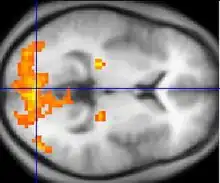

Il s'agit de la capture par une IRM de séquences spécifiques : des séquences echo-planar T2* (ce sont des séquences d'IRM spécifiques) permettant de mettre en évidence le signal BOLD. On obtient ainsi pour chaque voxel une valeur du signal Bold, l'ensemble des voxels correspondant à ce qui est appelé cartes paramétriques. La comparaison statistique des cartes paramétriques seuillées permet de créer des cartes d'activation. Lorsque ces cartes d'activation sont superposées à une IRM cérébrale standard, on obtient l'image classique d'une IRM fonctionnelle (cf l'image en début d'article). L'étude statistique plus poussée de ces cartes d'activation peut permettre de faire de la connectivité fonctionnelle, c'est-à-dire de faire un lien entre différentes zones cérébrales utilisées lors d'une même tâche.

Si l'IRMf permet de localiser dans un cerveau les zones activées par la réalisation d’une tâche simple, il faut cependant interpréter de façon adéquate les résultats. Une fois obtenues les images anatomiques et fonctionnelles du cerveau, elles doivent être traitées pour éliminer les faux positifs et les faux négatifs : « Les images anatomiques pour chaque sujet sont réalignées pour corriger le mouvement du sujet, puis sont alors co-enregistrées avec l’image fonctionnelle. L'analyse statistique permet de détecter les secteurs qui ont été significativement activés lors de l'expérience » [3]. Les images fonctionnelles peuvent être alignées sur une image anatomique individuelle ou encore sur un modèle anatomique moyen, qui représente un cerveau moyen intersujets. Ces images fonctionnelles dépendent du protocole qui est utilisé pour activer le cerveau, et donc pour isoler l’activité cérébrale qu’on veut observer[3]. Dans des protocoles expérimentaux simples, on peut utiliser le paradigme en bloc dit de soustraction ou de différence. « L’activité cérébrale est enregistrée au cours d’une condition neutre (ou de référence R) où le stimulus est présenté sans instruction particulière. Un deuxième enregistrement est effectué mais dans la condition dite cible. L’activité résultant de l’opération étudiée correspond à la « soustraction » de la mesure en condition cible par la mesure en condition neutre. Cette soustraction correspond à un test de différence statistique significative (test T par exemple) appliqué voxel à voxel et dont on peut faire varier le seuil »[3]. Étant donné que le cerveau n’est jamais dans un état d’activation complètement stable, il y a de bonnes chances de retrouver des artéfacts dans les données.